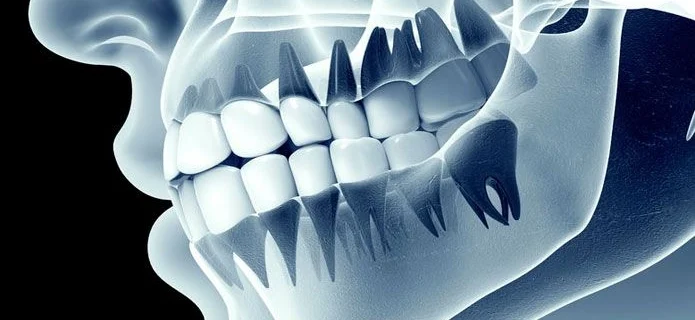

Sportovi i fizičke aktivnosti su izuzetno važni za očuvanje zdravlja i kondicije, ali isto tako mogu predstavljati rizik za vaše oralno zdravlje. Kontakt sportovi, kao što su fudbal, košarka, rukomet, ili čak rekreativne aktivnosti poput biciklizma i skejtborda, mogu dovesti do ozljeda zuba i usne šupljine. U Stomatološkoj Ordinaciji Hasanagić, želimo osigurati da vaši zubi …